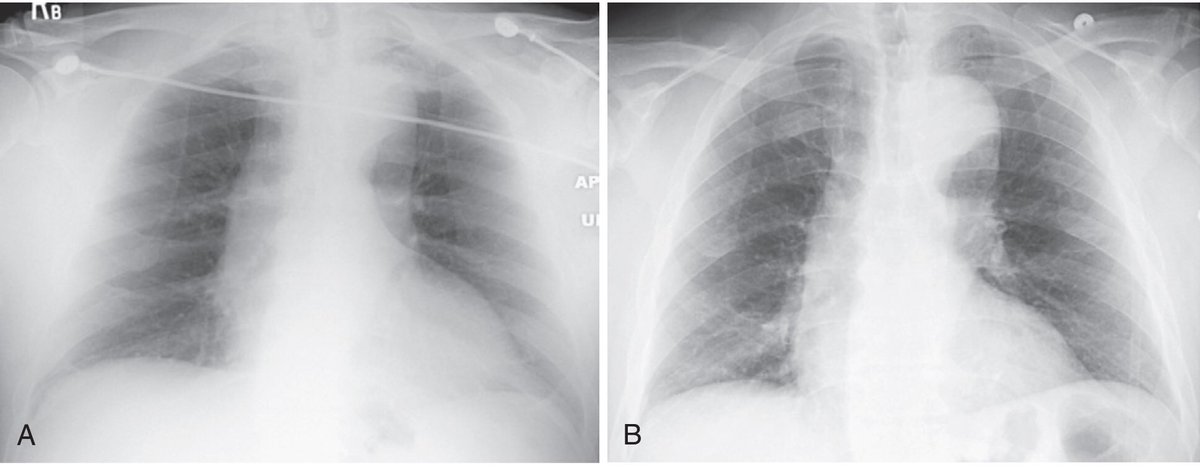

في الأشعة السينية للصدر يا الصورة تكون PA بمعنى posteroanterior

او AP بمعنى Anteroposterior

في الـPA مصدر الاشعة بيكون داخل للعيان من ورا على الضهر و الفلم البيستقبل الاشعة بيكون قدام العيان على صدرو

في الـAP مصدر الاشعة بيكون جايي من قدام العيان من جهة صدرو و بيقطع الجسم عشان يصل المستقبل القاعد ورا العيان على جهة ضهرو

القلب قاعد قدام في الصدر (anterior)

اذا الاشعة جات من قدام حتخبط في القلب اول و حيكون بعيد من الفيلم و الصورة بتاعت القلب حتكون اكبر

و اذا الاشعة جات من ورا فحتخبط فيهو آخر حاجة و حيكون قريب من الفيلم (المستقبل، الحيطة) و الصورة بتاعت القلب حتكون اصغر

بمعنى:

لمن الاشعة تجي من قدام فالقلب الضل بتاعو بيكون اكبر، ليه؟ عشان القلب المسافة بينو و بين المستقبل بعيدة شوية، زي لمن تبعد يدك من الحيطة و انت ضارب فيها فلاش؛ ضلها بيكون اكبر

لمن الاشعة تجي من ورا العيان و تمشي للمستقبل ف هنا القلب بيكون قريب من الحيطة و الضل حيكون اقرب للحجم الطبيعي

عشان كدا اذا كنت حتطلب صورة صدر للعيان و كنت مهتم تعرف اذا في تضخم في القلب او لا احسن تطلب الصورة PA view

Image from the book: Learning Radiology Understanding the Basics 3rd Edition, William Herring, MD